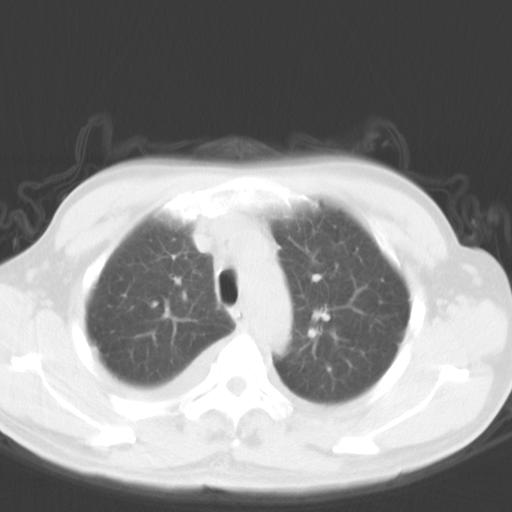

以下是引用zjzjr在2010-3-21 17:39:00的发言:[br]右下中心型肺癌并阻塞性肺炎/不张,纵膈淋巴结肿大,右侧大量胸腔积液,左侧少量胸腔积液

以下是引用zxl51642在2010-3-21 17:06:00的发言:[br]右下中心型肺癌并阻塞性肺炎/不张,纵膈淋巴结肿大,右侧大量胸腔积液,左侧少量胸腔积液,少量腹水。建议纤维支气管镜进一步检查。